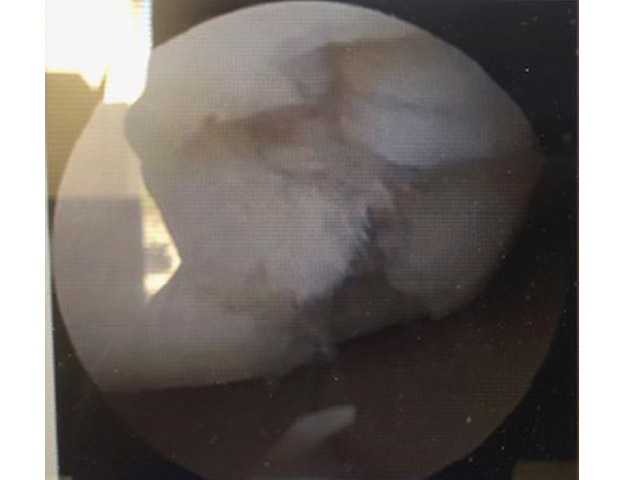

Patient did not want to go through a shoulder replacement. Had constant moderate to sever pain and very limited range of motion. Now pain is significantly reduced and increased range of motion. Quality of life is much improved.